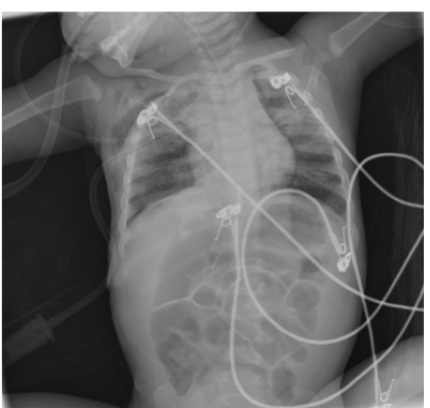

Complicated Community Acquired Pneumonia and Air Leak Syndrome, Case Report

Mona AlMarshood, Iman AlMukhtar, Mahammad AlOwa, Hani Hilal, Fadel Albasarah, Hussam AlSaffar, Maryam AlBasri, Kauther AlSadeq and Saleh AlHashim. 11(12): 69-78.